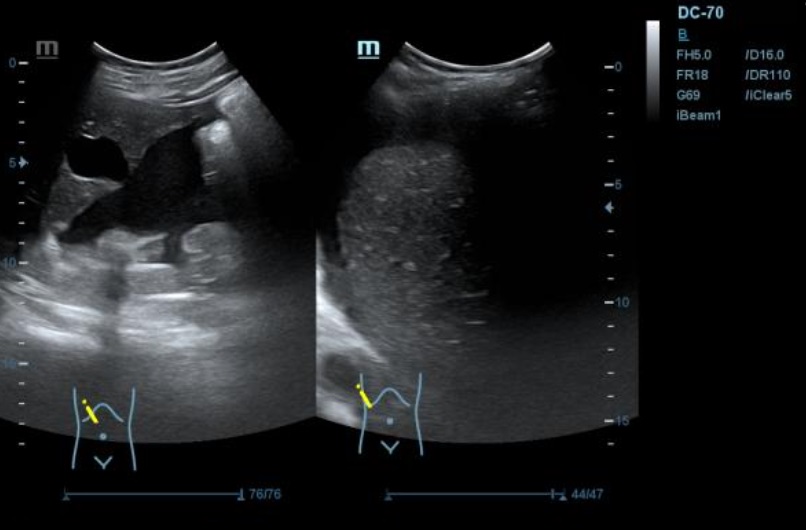

Ecografía: se observa presencia de líquido ascítico, e imagenes en hipomesogastrio hipo e hiper ecogénicas, tabicadas algunas, con efecto masa, con vascularizacion al Doppler que sugieren carcinoma de ovario.